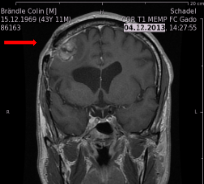

we treat the brain tumor using the latest technologies. Our efforts have saved many lifes and looking forward for many more